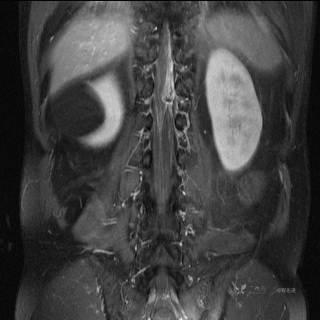

MR

T1

T1增强